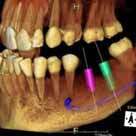

volumeをXYZ方向にそれぞれ512分割しておりこのときのスライスピッチは標準モード撮影で147㎛、高解像度モード撮影(ハイレゾ)で101㎛です。 3D画像はリアルタイムで自由に動かすことができるので骨の形態や奥行きを容易に把握できます。 さらにウィンドウレベルを操作することでさまざまな画像を簡単に得ることができます。 またインプラント治療においては下顎管やオトガイ孔、上顎洞下壁までの距離を正確に測定できるので術中も安全に治療をおこなうことができます。 |

人工骨(β-TCP)を用いてソケットリフトを行い

インプラント埋入。(前頭断)

同上。(矢状断)

(直径5㎜被覆長8㎜)